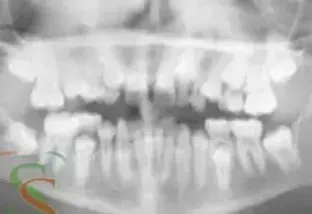

Radiologia

La teleradiografia è una radiografia da cui si ottiene un'immagine...